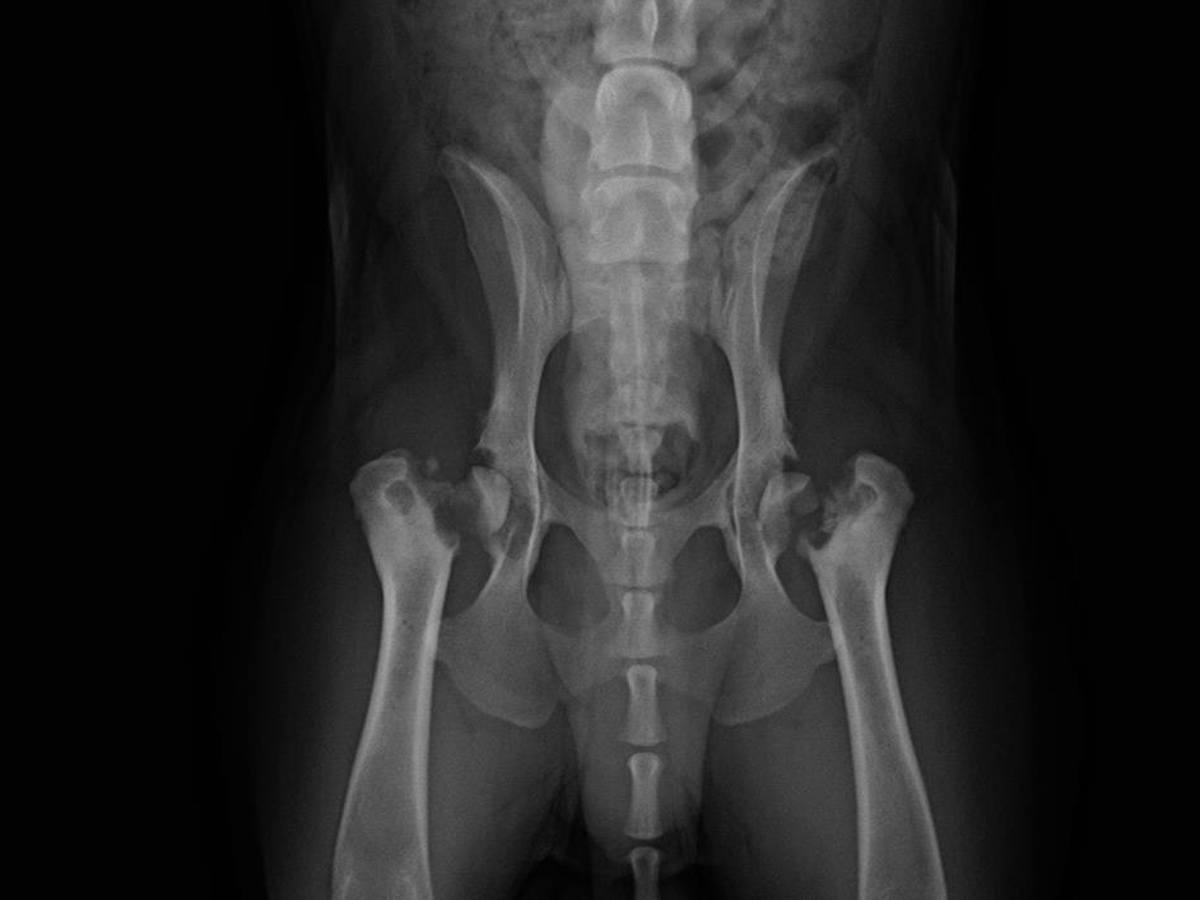

It’s Dr. Rebecca Coil again. We have another Animal Control patient who needs your help urgently. Lil’ Joe is a 10-month-old petite, sweet, gentle bully previously owned by a houseless individual. He was very thin and limping severely. On X-rays, we discovered he was suffering from fractures of both of his hips, most likely due to severe trauma, like being hit by a car. It took time for Animal Control to gain custody of Lil’ Joe to have the authority to give him the treatment that he desperately needs. Unfortunately, the animal control budget is limited, so the only option given by Animal Control was euthanasia.